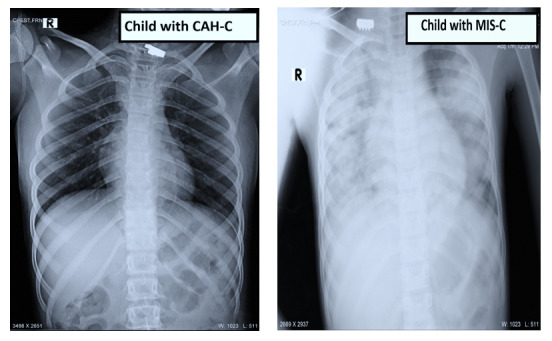

Background: Although the pediatric population has largely remained free of severe COVID-19 symptoms, in some cases, SARS-CoV-2 infection has been associated with complications such as multiple inflammatory syndrome in children (MIS-C). We identified another a unique form of hepatitis occurring subsequent to asymptomatic SARS-CoV-2 infection, designated by us as COVID-19-associated hepatitis in children (CAH-C), in a subset of children who presented with hepatitis.

Results: Among the 5539 children tested for SARS-CoV-2, a total of 475 (8.6%) tested positive and 47 (0.8%) presented with hepatitis. Among the 47 children with hepatitis, 37 (79%) had features of CAH-C: having symptoms of hepatitis only, without protracted illness (mean length of stay 5 d), and an uneventful recovery following supportive treatment. In contrast, the remaining 10 (21%) had features of MIS-C-associated hepatitis: multiple system involvement; protracted illness (mean length of stay 8 d); and requiring admission to critical care, with a mortality rate of 30% (3/10).